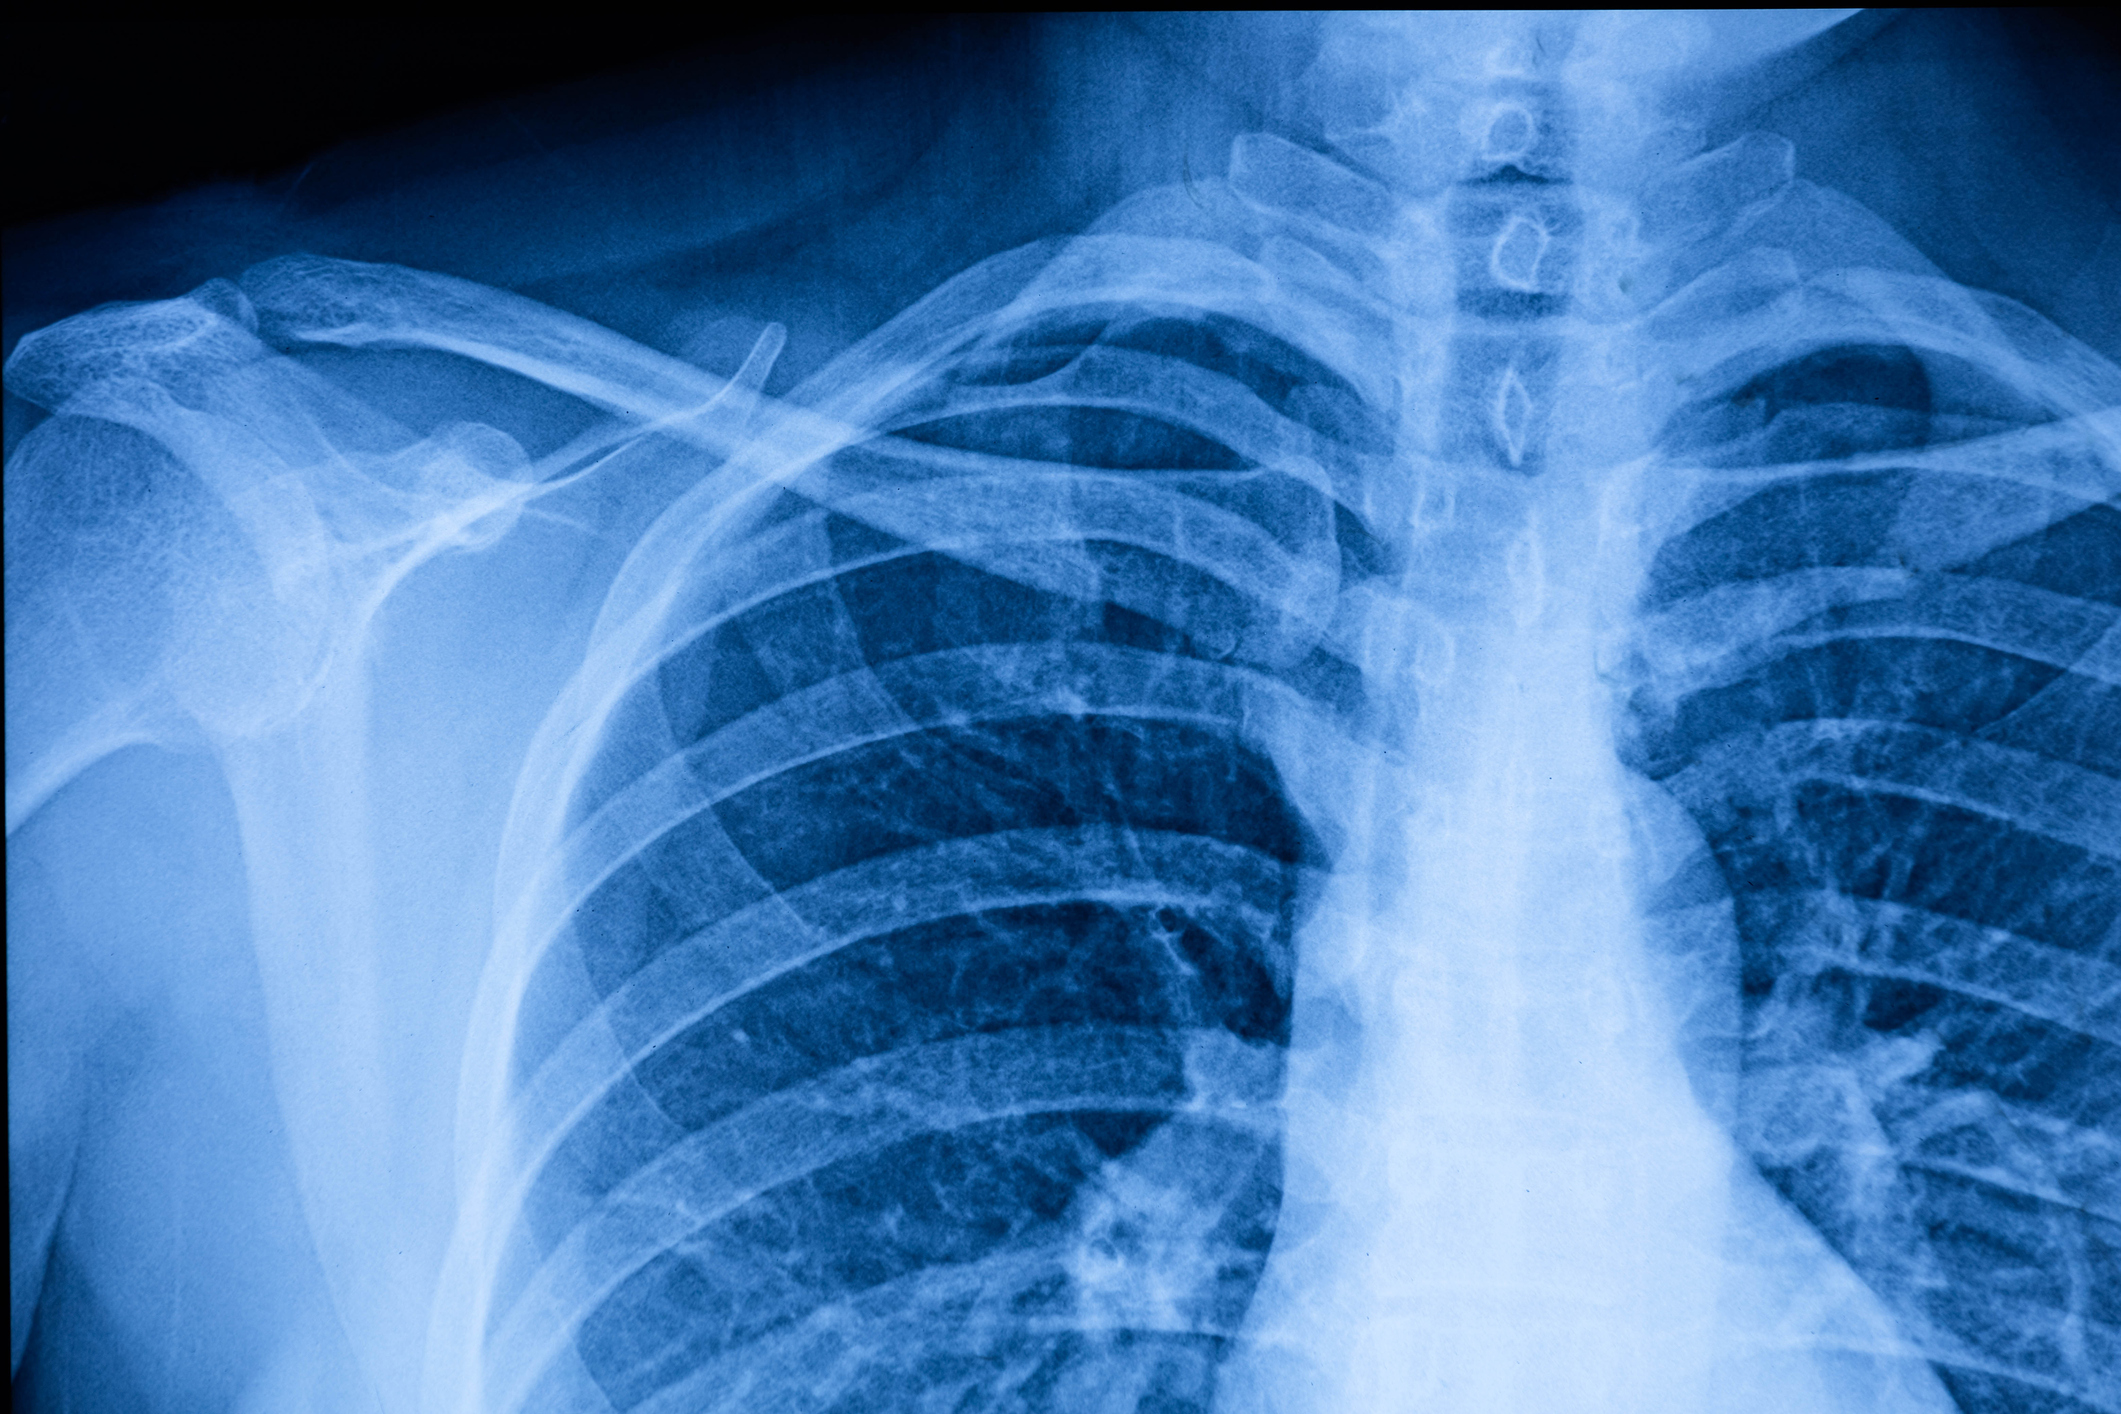

Future Doctors – “Read the Radiograph” Workshop

In our Read the Radiograph Workshop, you’ll learn how doctors interpret X-rays to uncover what’s happening inside the body. From fractures to lung shadows, this session walks you through real cases and teaches you how to analyze radiographic images like a future clinician. Perfect for students from high school to medical school—no prior experience needed. Seats are limited, so sign up now and start seeing medicine through a whole new lens.